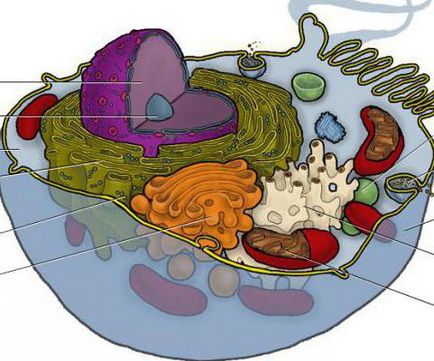

Áttekintést ad az emberi test, az első helyen tesszük a ketrecben. Ez a legkisebb szerkezeti és funkcionális egységet. Az emberi test - több mint kétszáz fajta sejtek, amelyek mindegyike saját szerkezete, funkcionális szerkezet. Ha figyelembe vesszük az általános szerkezet a terv, ez ugyanaz. A héj, a citoplazma és a sejtmag - a fő összetevői a cellában. A burkolat képez glycocalyx és plasmalemma. A citoplazmában és sejtszervecskék különböznek hyaloplasm.

A sejtfal egy receptor funkció, szelektív permeabilitás, átadása elektromos és kémiai jelek, elválasztja a sejtközötti a protoplazma.

A fő tulajdonságai a sejtek alapvető aktivitás ingerlékenység, az anyagcserét, szaporodást, öregedés, a halál.

Anyagcsere folyamatosan zajlik. A cella folyamatosan magában foglalja a különböző érintett anyagok az energia és a műanyag anyagcsere eredetű komponenseket használjuk, a hőenergia szabadul.

A sejt képes reagálni a különböző belső és külső ingerekre. Válasz Form - ingerelhetőség, ez jár a sejtmembrán töltés.

Minden sejt saját életciklusát. Minden nap, az emberi test körülbelül 1-2% -a a sejtek elhalnak eredményeként az öregedés és indítson új, az eljárás folyamatos.